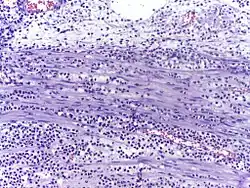

Micrograph showing several neutrophils during an acute inflammation

Low neutrophil counts are termed neutropenia. This can be congenital (developed at or before birth) or it can develop later, as in the case of aplastic anemia or some kinds of leukemia. It can also be a side-effect of medication, most prominently chemotherapy. Neutropenia makes an individual highly susceptible to infections. It can also be the result of colonization by intracellular neutrophilic parasites.

In autopsy, the presence of neutrophils in the heart or brain is one of the first signs of infarction, and is useful in the timing and diagnosis of myocardial infarction and stroke.